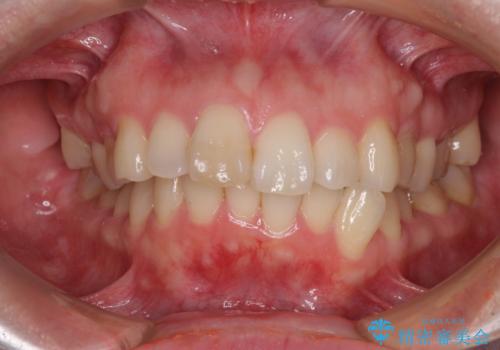

- 上顎前歯の突出感と、前歯のクロスバイトを気にして来院された患者様です。

前歯の叢生と口元の閉じにくさを気にして来院された患者様です。

カリエール・ディスタライザーを用いたことで上顎前歯の突出感はスムーズに解消され、歯列不正は1年半ほどでほぼ改善することができました。